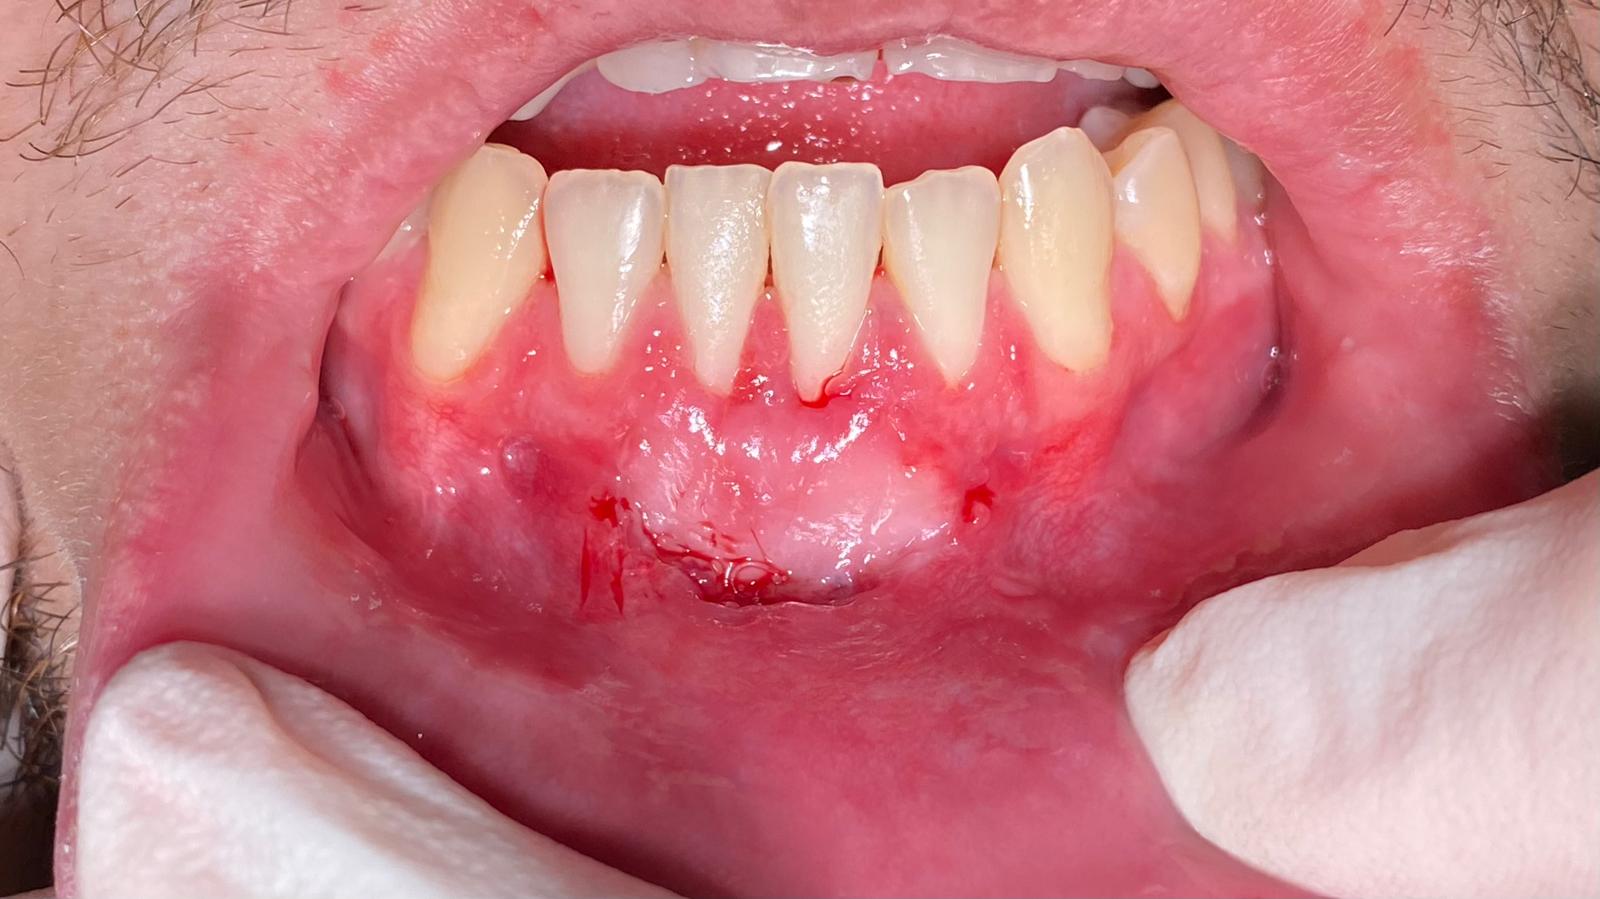

Gingivectomía e injerto de encía

Si tienes asimetría gingival, encías retraídas o demasiado visibles, podemos mejorar su forma y salud con técnicas quirúrgicas mínimamente invasivas. El resultado es una sonrisa más armónica y estética.